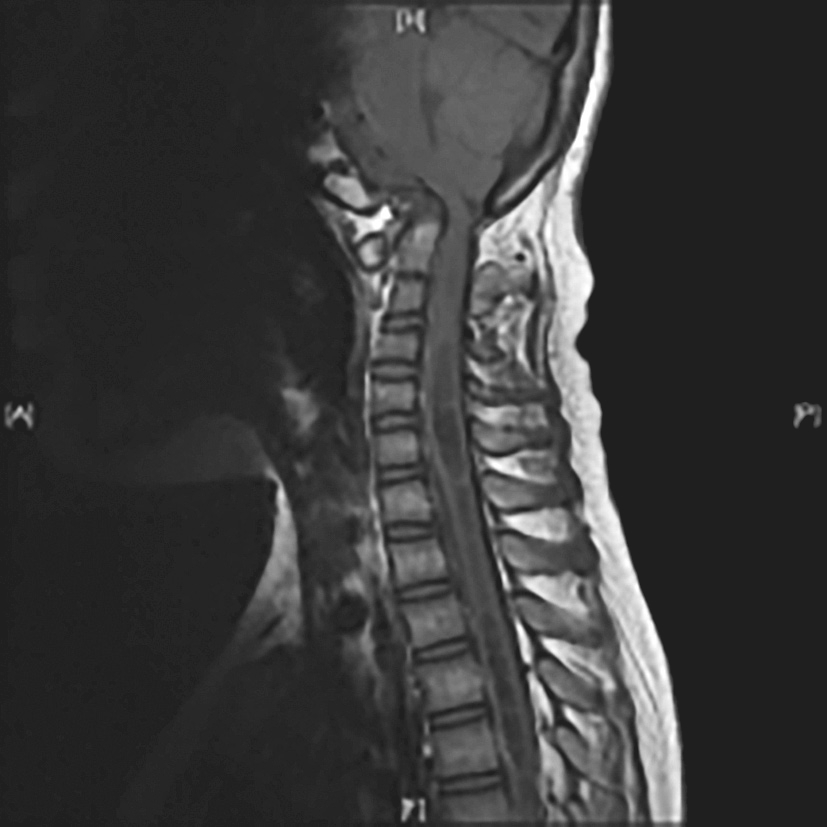

1.常见影像学测量指标(图4-4-1)

图4-4-1 常见影像学测量指标

1.钱氏线;2.Wackenheims线;3.McRae线。

(1)钱氏线:正常时齿突尖低于此线(2.3±2.6)mm,齿突尖高于此线3~5mm考虑颅底凹陷。

(2)麦氏线:又称基底线,正常时齿突尖低于此线(0.8±3)mm,齿突尖高于此线6mm考虑颅底凹陷。

(3)McRae线:正常时齿突尖低于此线(5.8±1.6)mm。

(4)Wackenheim线:指沿斜坡背侧面向下延伸的直线,正常时齿突与其相切或略低于此线(0.9±2.2)mm。

(5)寰齿前间距:为寰椎前弓后缘与齿突前缘之间的距离。成人超过3mm(<13岁儿童超过4mm)或动态(前屈后伸位)测量变化超过2mm均可考虑寰枢椎脱位。

(6)寰齿后间距:寰齿后间距对于反映慢性寰枢椎脱位更为敏感,SAC<19mm常有症状,一般将13mm作为诊断阈值。

(7)BDI值:前屈后伸功能位时BDI值变化应小于1mm,>1mm提示寰枕不稳定,头部中立位BDI>12mm提示发生寰枕关节前脱位或分离脱位。

(8)BAI值:正常成人BAI一般不超过12mm。BAI>4mm提示寰枕关节后脱位或分离脱位;BAI>12mm时提示寰枕关节前脱位或分离脱位。

(9)Powers比:该值正常为0.7±0.09,>1时考虑寰枕关节前脱位。

(10)斜坡-椎管角:正常时该角度150°(屈曲位)~180°(伸展位),小于150°时常存在脑干脊髓受压。

(11)脑干-颈髓角:正常时该角度150°~180°,小于150°时常存在脑干颈髓受压。

(12)基底角:正常值120°~140°,大于140°时考虑扁平颅底。

(13)寰枕关节角:正常124°~127°,角度增大考虑存在枕骨髁发育不良。